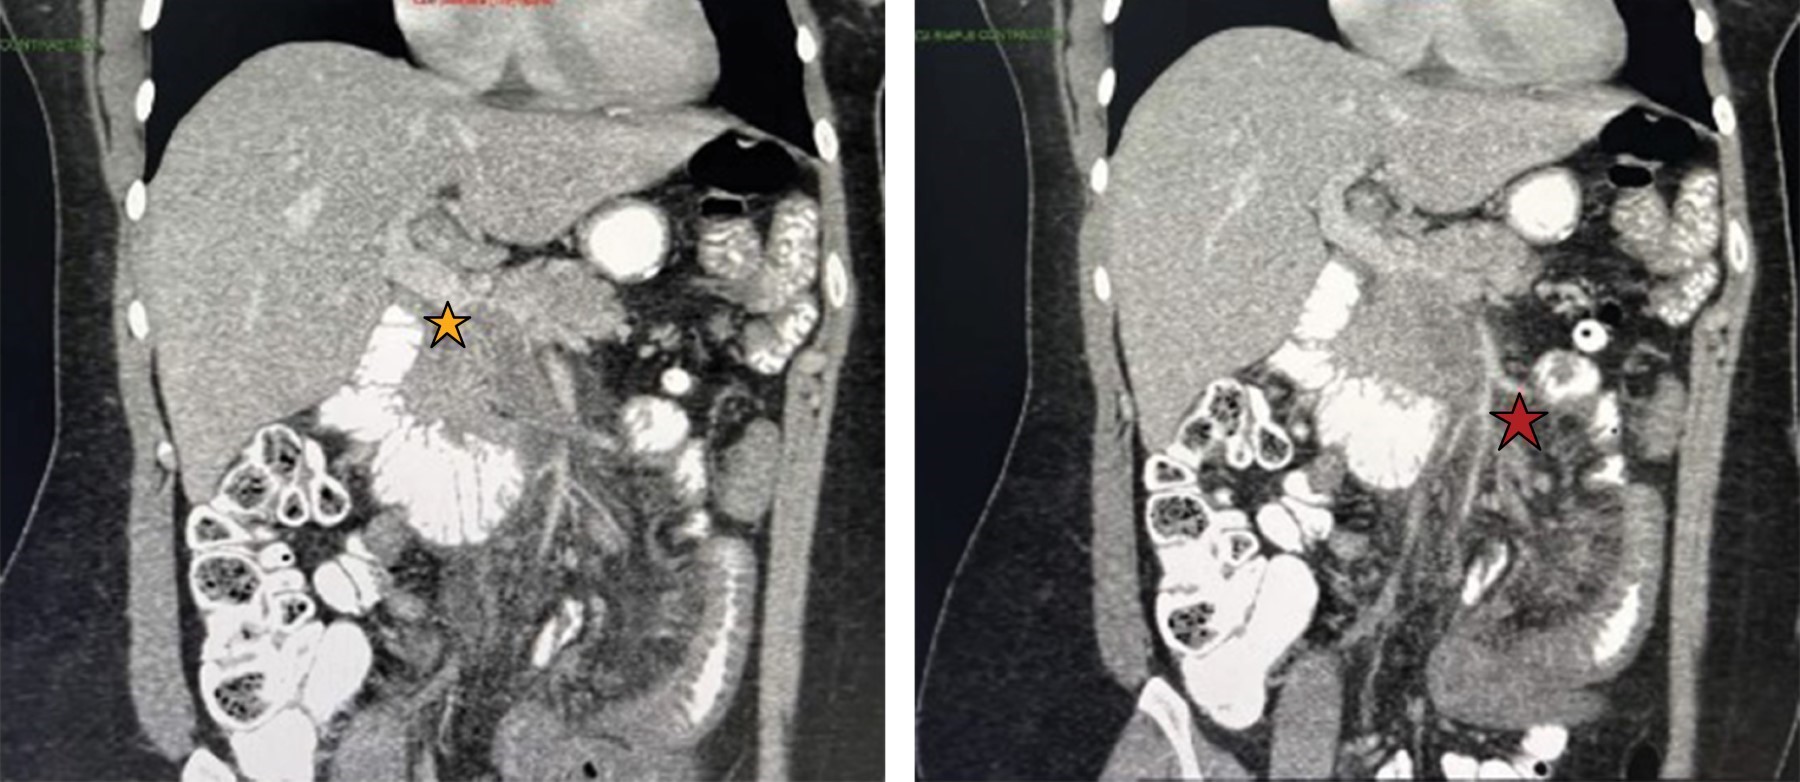

Introduction: An acute case of intestinal ischemia is a surgical emergency that could lead to abdominal sepsis, mesenteric or bowel infarction or even death. Amongst the new available measures to make an early diagnosis is the use of indocyanine green which has been used in hepato-biliary and oncologic surgery amongst others. However, there are only a few reports in the literature about its use in intestinal ischemia. Clinical case: This is the case of a 33-year-old female with abdominal pain and tomographic findings of an extense filling defect involving venous ileal branches, the superior mesenteric vein and partially the portal vein secondary to thrombosis and changes in the small bowel suggesting bowel ischemia. An exploratory laparoscopy was performed using indocyanine green to evaluate intestinal perfusion ruling out ischemia or necrosis. After further evaluation and with a multidisciplinary management to rule out prothrombotic states a second-look laparoscopy was performed using indocyanine green corroborating an adequate intestinal perfusion and intestinal viability. Her post-operative evolution was favorable and was discharged home. Conclusion: This case exemplifies how the use of indocyanine green has useful applications in the management of intestinal ischemia and can avoid unnecessary bowel resections.

Figure 3